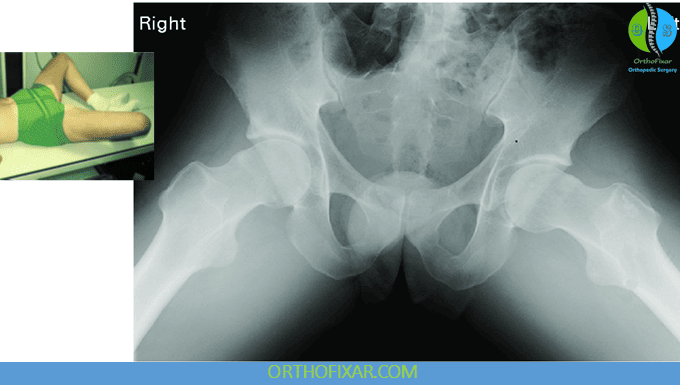

Lateral (Axial “Frog-Leg”) View

The frog-leg lateral hip x-ray is obtained with the patient supine and the hips placed in flexion, abduction, and lateral rotation. This positioning produces a true lateral view of both the femoral head and neck.

Clinical applications:

- Avascular necrosis (AVN): Early contour irregularities or sclerosis may be detected.

- Slipped Capital Femoral Epiphysis (SCFE):

- The frog-leg lateral view is often the first projection in which the slip becomes visible, making it essential in suspected SCFE.

- Posterior and inferior displacement of the epiphysis relative to the metaphysis can be appreciated.

- Head-neck offset deformity: Used to assess morphology relevant to cam-type FAI.

- Pelvic distortion or rotational malalignment can also be detected.

This view therefore plays a critical role in early detection of both growth-related hip disease (e.g., SCFE, Perthes) and structural abnormalities contributing to impingement or instability.